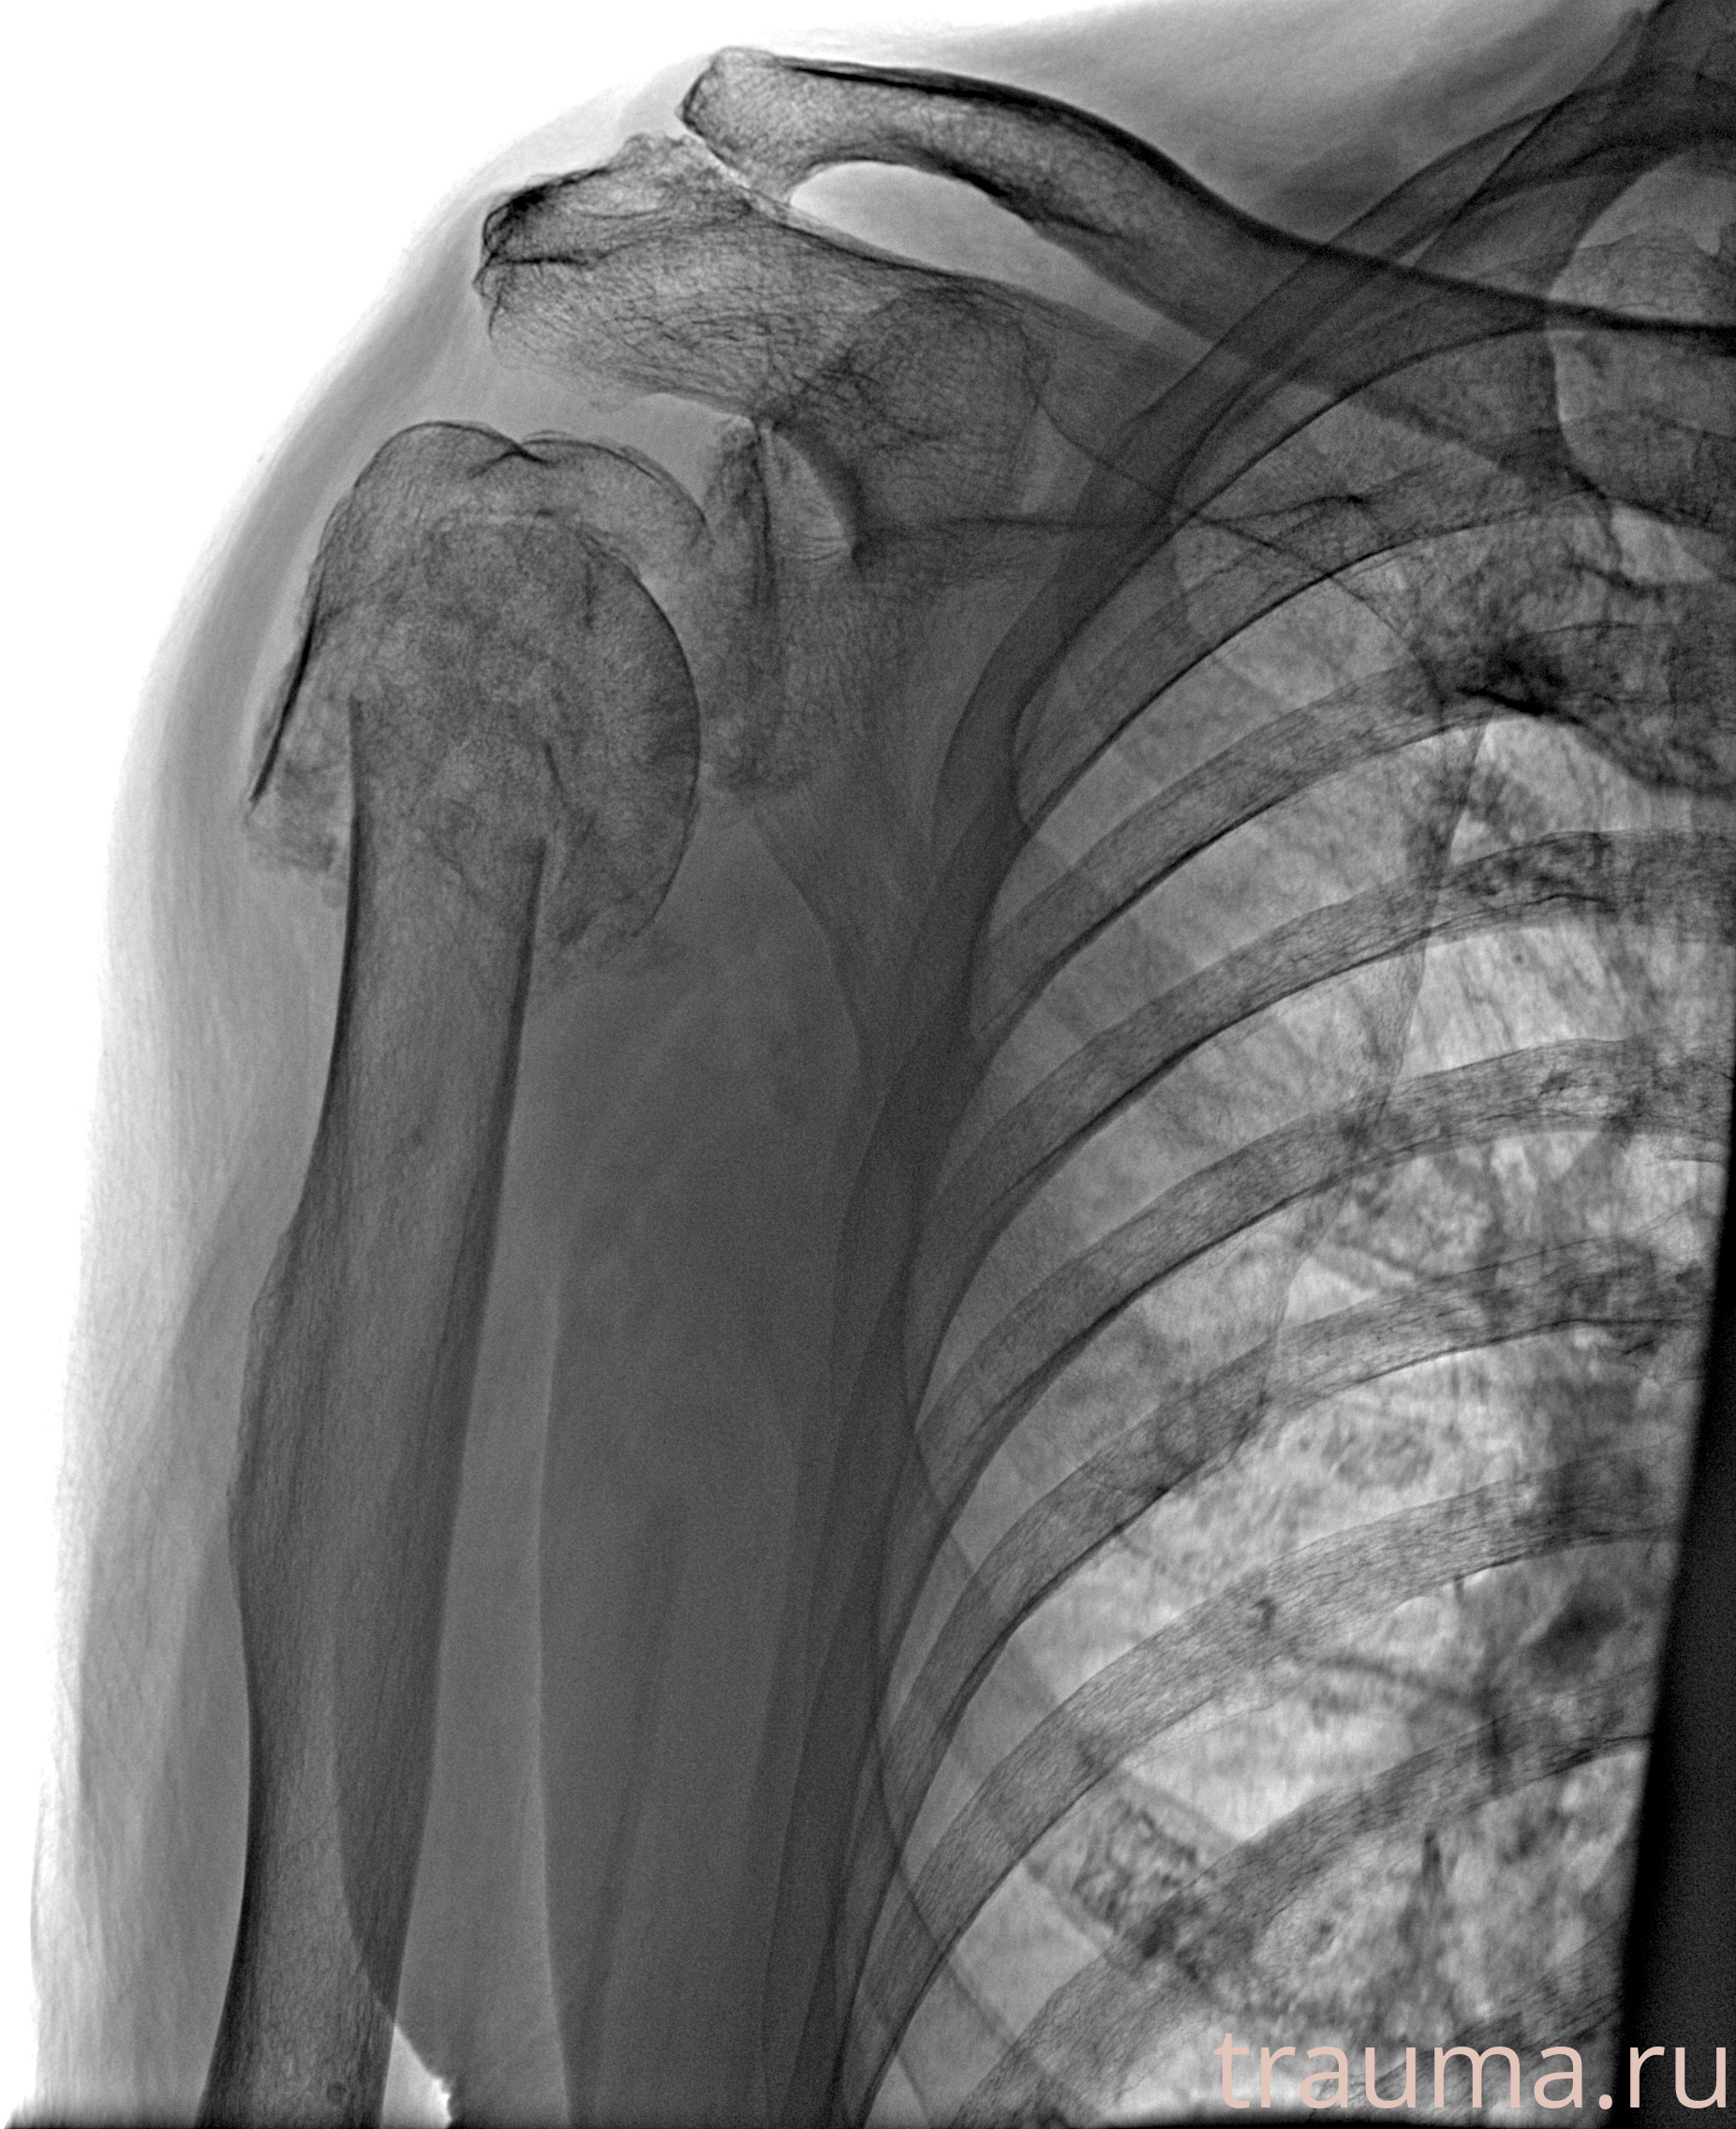

Рентгенограммы

Рентген на дому: по вашему адресу приезжает врач-рентгенолог, травматолог-ортопед с мобильным рентгеновским аппаратом, проводит диагностику травмы или заболевания, делает необходимые рентгенограммы, дает рекомендации по дальнейшему лечению. Получить качественные снимки в домашних условиях возможно благодаря уникальной методике, разработанной МосРентген Центром для института  Склифосовского